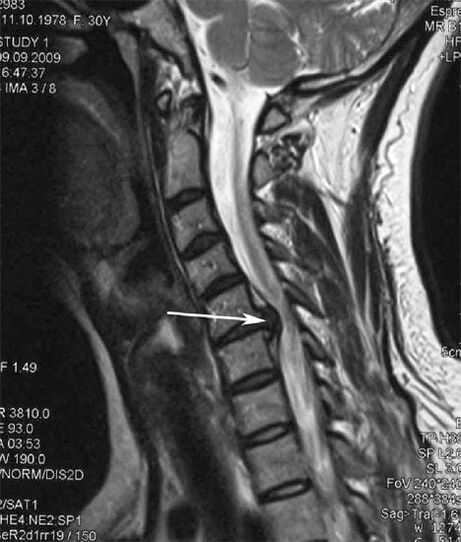

In the initial stages, osteochondrosis is detected with the help of MRI.Later, the pathology can be diagnosed using radiography.On the X-ray of the cervical spine, a decrease in the distance between the vertebrae, pathological changes in the facet joints and osteophytosis are noted.

| Cervical osteochondrosis | The appearance of pathological changes in one or more spinal motor segments.Impaired mobility of the spine, development of myofascial pain syndromes and pinching of spinal roots | Pain, paresthesia and movement disorders in the cervical region, which spread to the back of the head and upper limbs.Detection of characteristic changes in the spine on MRI and X-rays (osteophytes, reduced distance between the vertebrae, signs of damage to the intervertebral joints) |

Many people complain that they cannot turn their neck due to severe pain that occurs after suddenly lifting something heavy.This phenomenon indicates the formation of a disc herniation.The cause of the pain in the back, neck and upper limb is a pinching of one of the nerve roots coming out of the spinal cord.